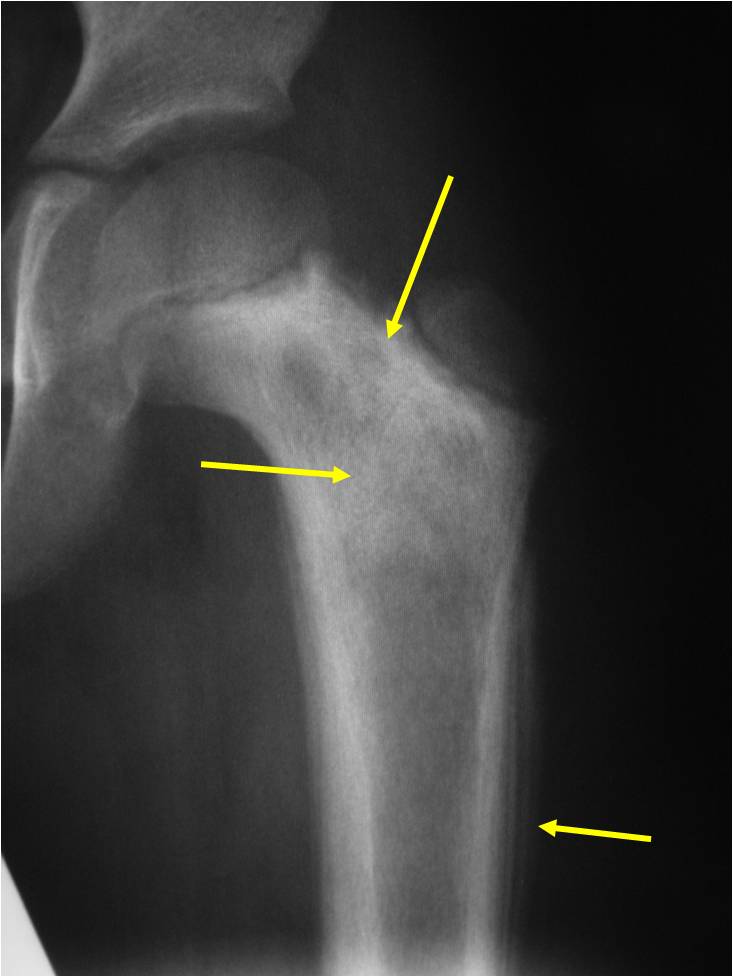

- • The work-up for Ewing’s Sarcoma often consists of a physical examination, X-rays, CT scans, or MRI of the effected bone. A Whole Body Bone Scan may be ordered to determine if the tumor metastasized, or spread.

An example of an MRI depicting Ewing’s sarcoma in the lower extremity is shown.